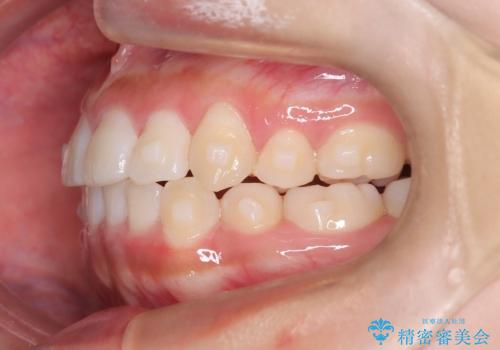

- 前歯のでこぼこが気になると来院されました。

奥歯の噛み合わせは綺麗に噛んでいたため、前歯の叢生(でこぼこ)を、短期間で治療完了するように計画しました。

前歯のガタツキを改善する治療法として、マウスピース矯正が適していることが多いです。

マウスピース矯正は、金属製のブラケットやワイヤーを使用せずに、透明なマウスピースを装着して歯を移動させる方法です。そのため、目立たず、痛みも少ないです。